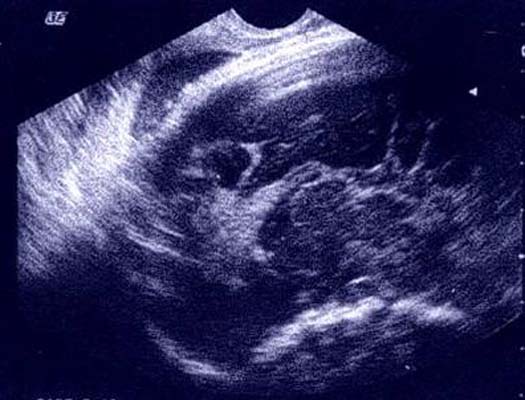

Lipome intra-cranien